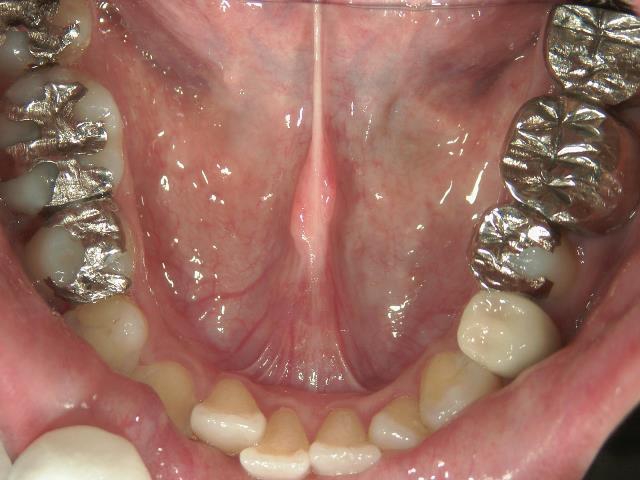

矯正歯科 治療前 上顎を装置(QH)で拡大後ワイヤー矯正へ移行、右下5番左下4番 計2本抜歯叢生改善

矯正_灰色.pngno.28_6958_治療前_下.jpg矯正_灰色.png